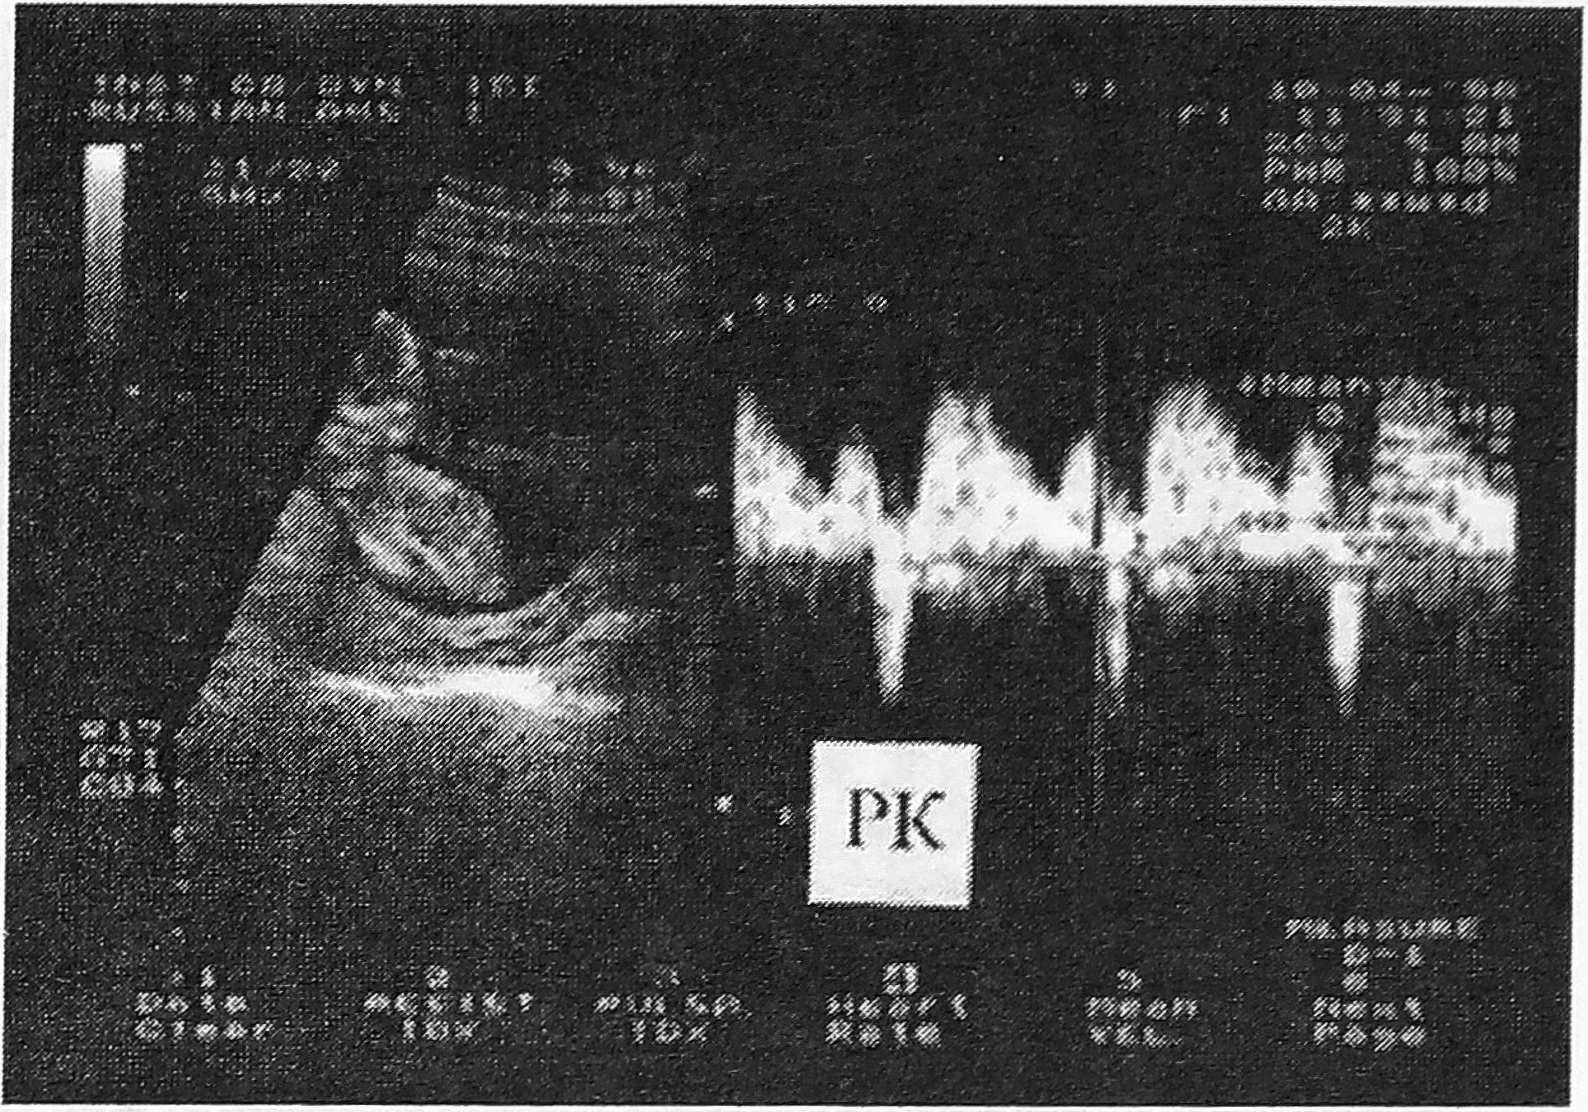

Спектр кровотока в нижней полой вене является трехфазным. Фазы спектра кровотока определяются работой сердца плода: I - систолой желудочков, II - периодом их пассивного наполнения в диастолу, III - сокращением предсердий. При этом спектр кровотока включает два компонента - ортоградный, который отражает движение крови к сердцу (I и II фазы), и ретроградный (отрицательный, III фаза), отражающий движение крови от сердца (рис.4). Отрицательный компонент наблюдается у всех плодов в первой половине беременности и у большинства плодов в ее второй половине. Величина ретроградного кровотока со сроком беременности уменьшается, что выражается в снижении соответствующего показателя - удельного веса (процента) ретроградного кровотока (УРК) и свидетельствует о снижении давления в правых отделах сердца плода, куда поступает кровь из нижней полой вены (рис. 8).

Рис. 4. Допплерограмма кровотока в нижней полой вене. РК - ретроградный кровоток.